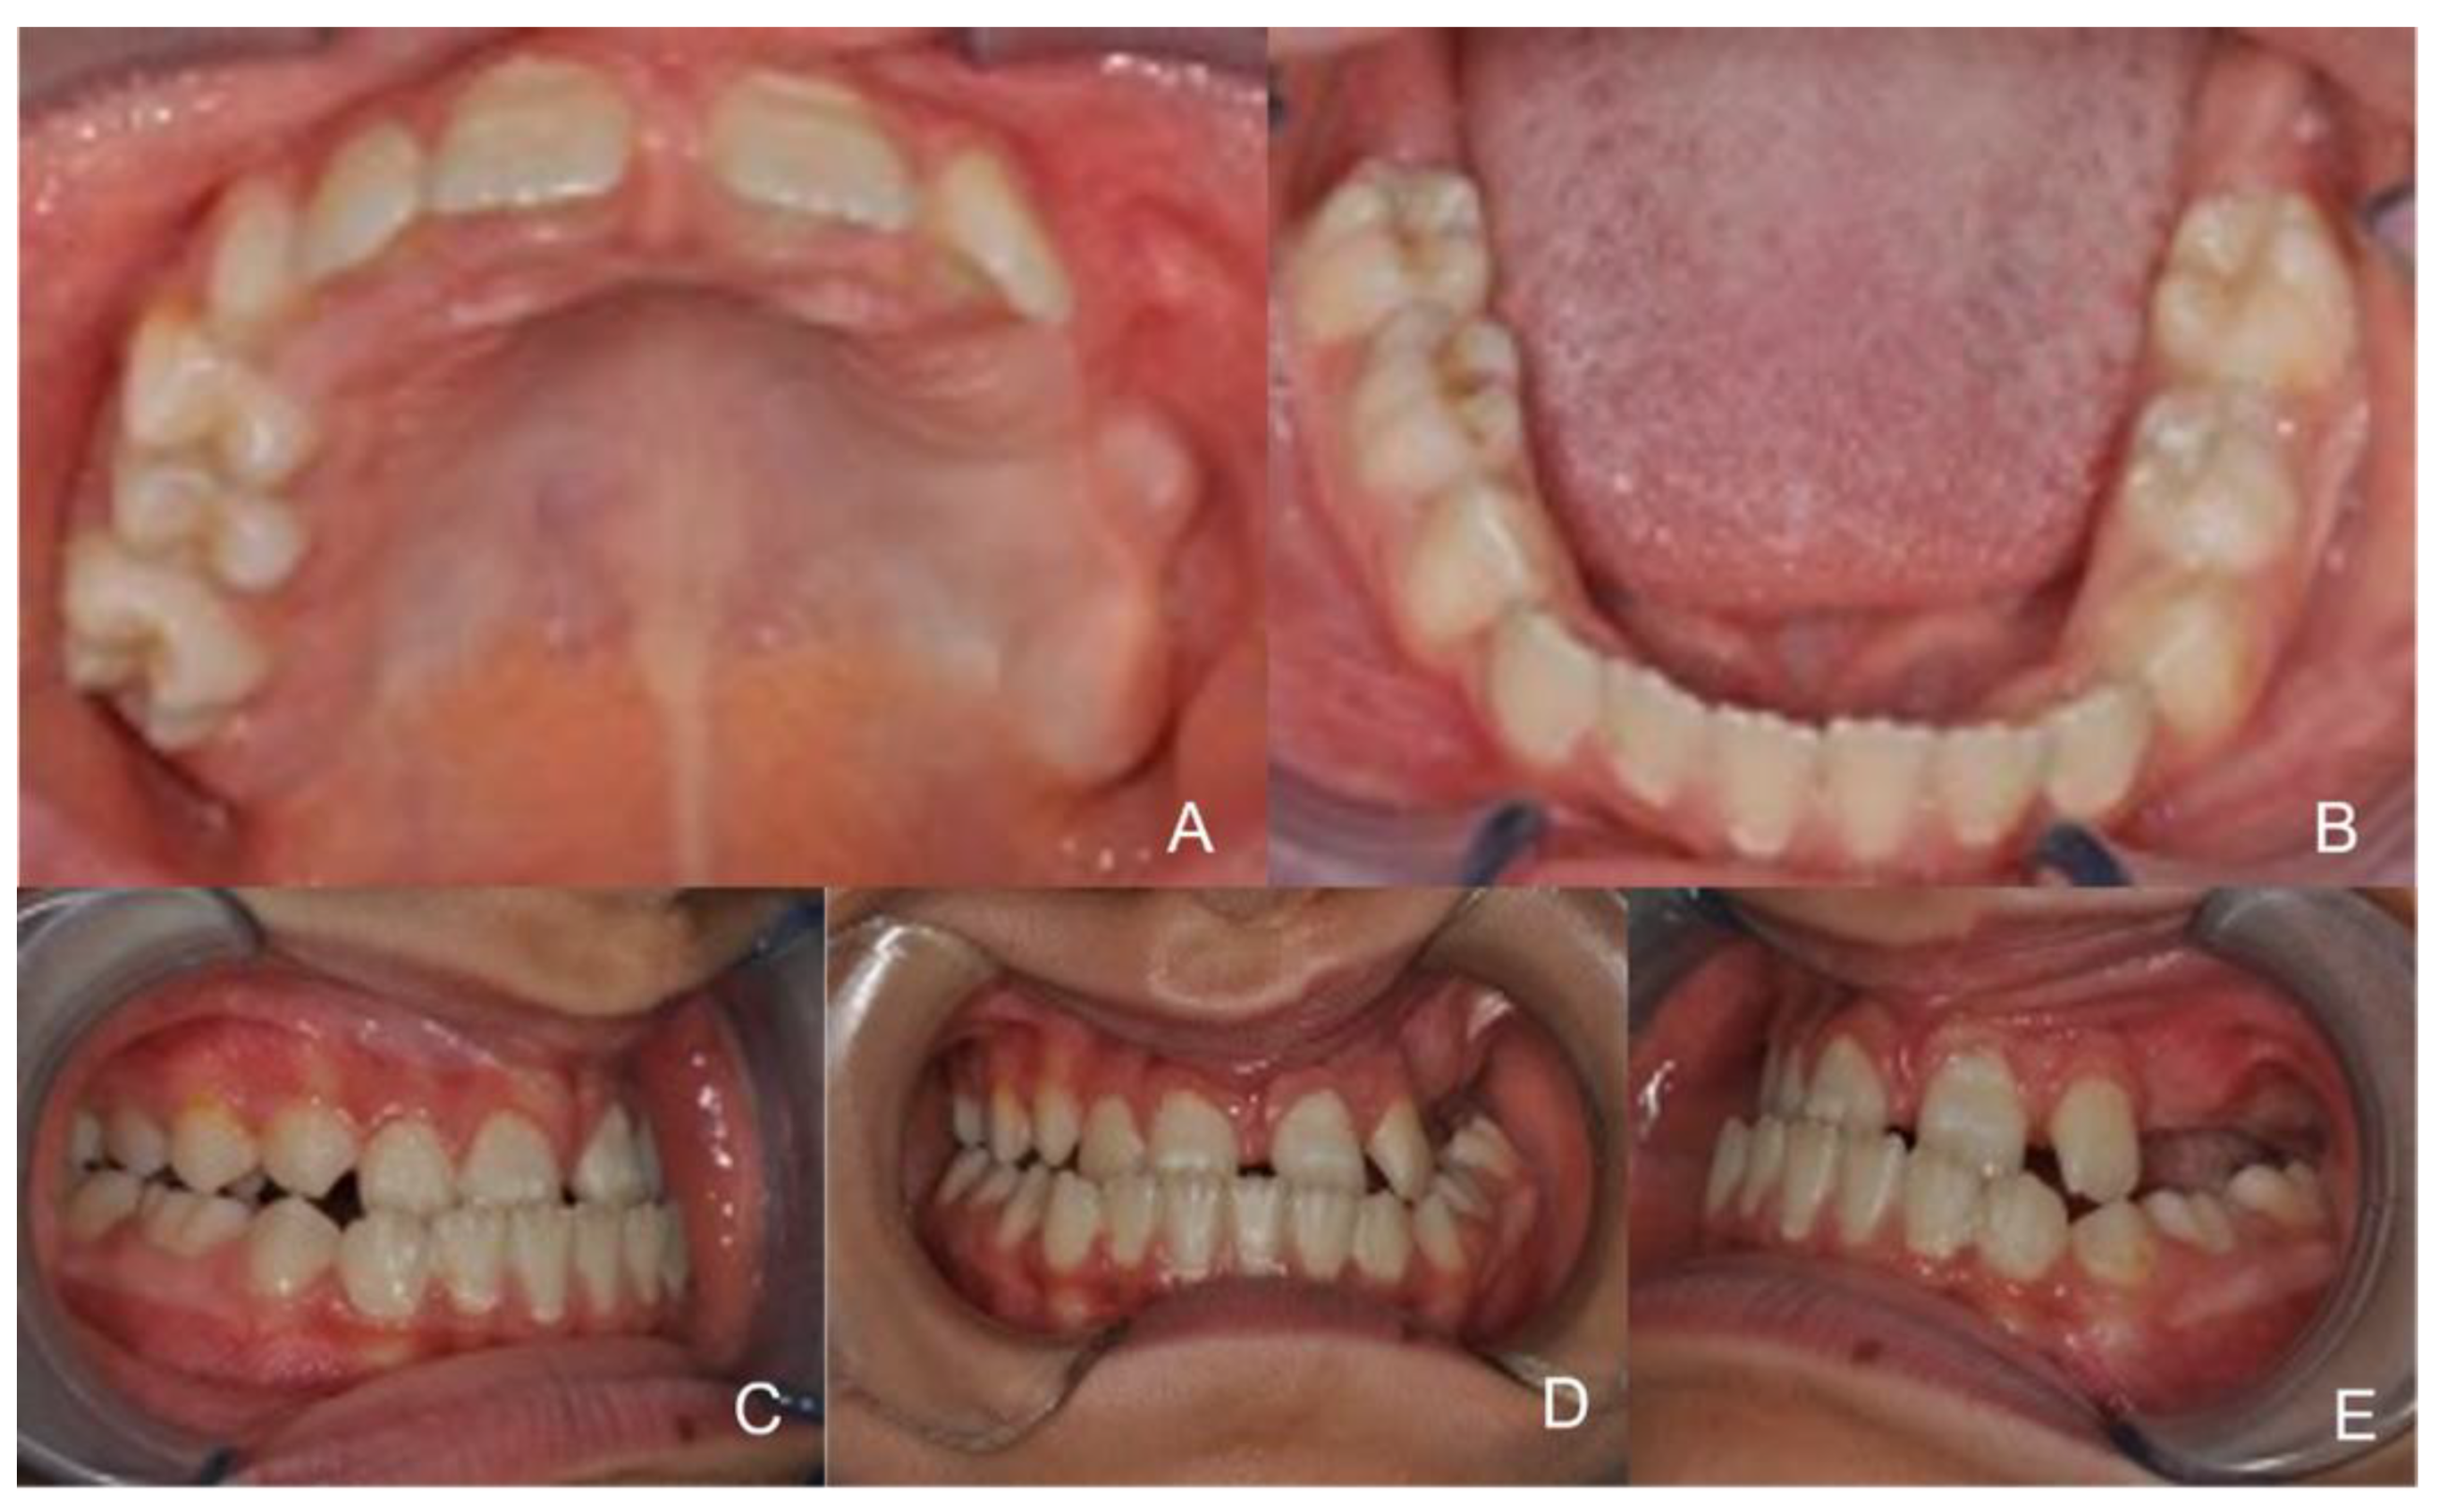

The patients of the PE group. A) The facemask of the protraction Face Mask Orthodontics Uses Class iii elastics were applied to the canine and. Orthodontic face masks (ofms) are orthodontic devuces used to prevent tooth movement during treatment. Facemask therapy with skeletal anchorage showed a greater advancement of the maxilla and more favorable stability for. They can be used as a preventive measure or may be On the other hand, early protraction facemask therapy could. Face Mask Orthodontics Uses.